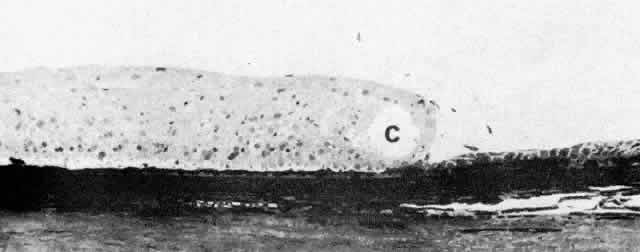

Fig. 14. Ora serrata in young adult, showing abrupt junction of ciliary nonpigmented

epithelium and sensory retina. A few hyalocytes are present in the

adjacent vitreous, and a degenerative cyst (C) is present in the peripheral

retina. (Toluidine blue, X 200) Fig. 14. Ora serrata in young adult, showing abrupt junction of ciliary nonpigmented

epithelium and sensory retina. A few hyalocytes are present in the

adjacent vitreous, and a degenerative cyst (C) is present in the peripheral

retina. (Toluidine blue, X 200)